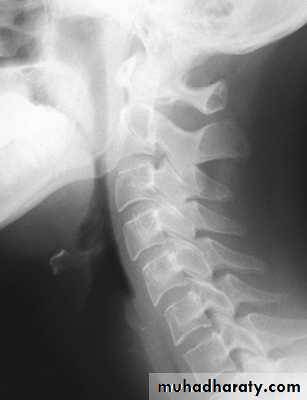

Cervical Spine X-RayLateral radiograph

A/P radiographThoracic Anatomy